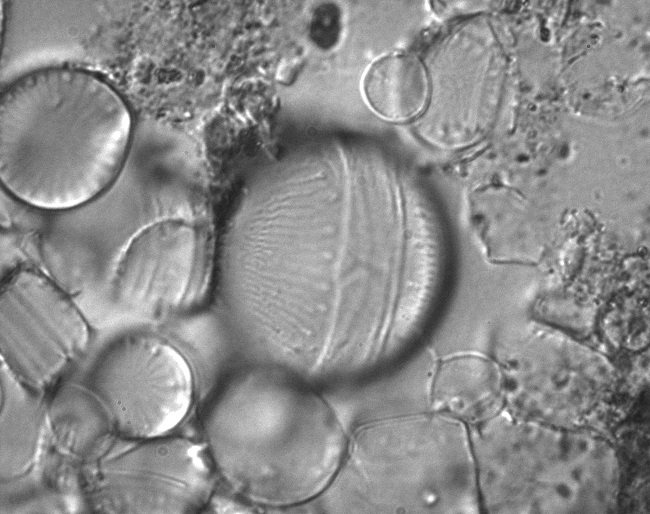

L’eau de distribution urbaine ne contient pas ou très peu de diatomées. En conséquence, cette méthode d’analyse reposant sur la comparaison des taxons présents en milieu d’immersion et ceux retrouvés dans les prélèvements de viscères ne peut être utilisée dans ce cas.